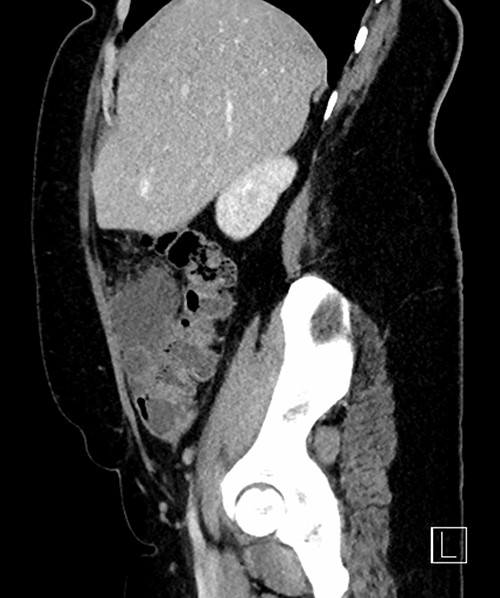

The white cell count was 10.5 × 109/l, C-reactive protein 6.8 mg/l, B-hCG negative, urine culture negative. Ultrasound (US) abdomen did not identify the appendix or the right ovary but noted a 102 × 43 × 52 mm complex multi-locular cyst. Computed tomography (CT) abdomen showed a focal low-density mass with adjacent inflammatory change anterior to the ascending colon measuring 43 × 55 × 54 mm (Figs 1–3). This mass appeared separate to the ovary and the appendix.

Sagittal CT reconstruction highlighting location of mass anterior to ascending colon.